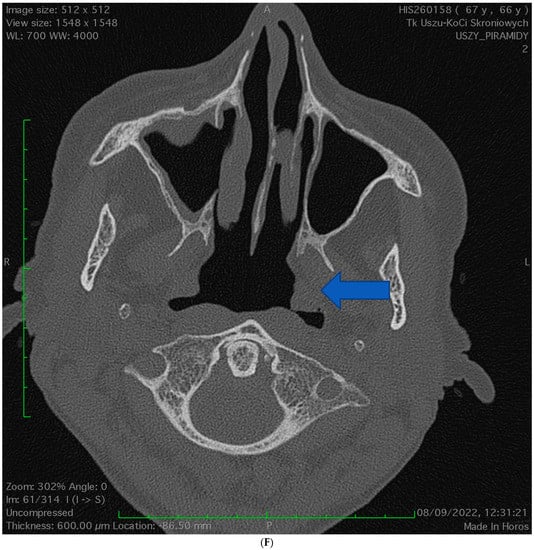

2.1. Case 1

2.2. Case 2

2.3. Case 3